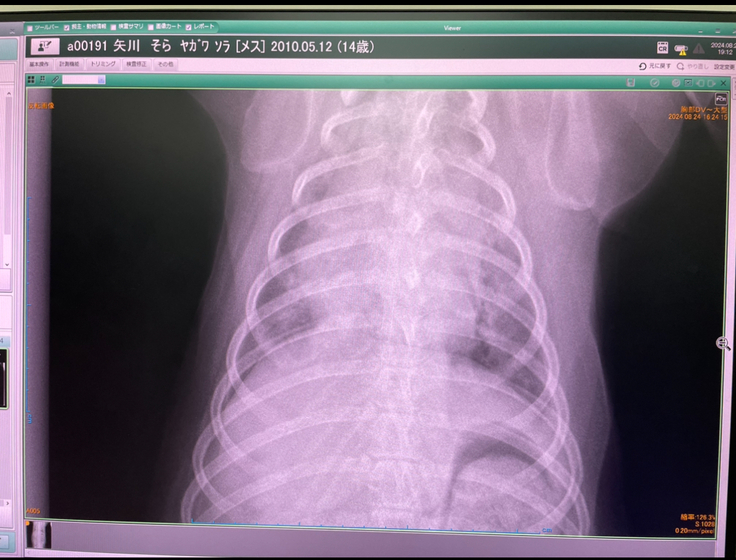

※掲載許可取得済み

2024年9月15日〜28日

当初診察していただいていた病院Aから循環器の専門病院Bを紹介いただき、レントゲン、エコー、内視鏡検査などを行った結果、僧帽弁閉鎖不全を発症しており、心臓からの血液逆流は見られるが、症状は軽微なもので肺水腫に至るようなレベルではなく、今回の不調は喉の異常が原因で喉頭麻痺という病気の診断を受けました。